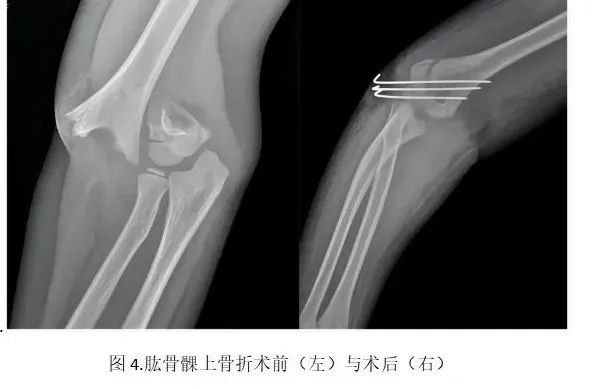

肱骨髁上骨折好发于5~8岁儿童,发病率占小儿肘部骨折的50%~70%,并发症颇多,处理不当易引起肘内翻。

微创手术是指在透视监视下复位骨折,经皮肤使用2-3根直径1-2mm克氏针固定骨折断端,克氏针尾部外露于皮肤表面,待骨折稳定后可于门诊拔除,无需二次住院取出。

该方法无手术切口,仅在皮肤表面残余2-3处直径1-2mm左右伤口,愈合后几乎无疤痕。在拔除克氏针后受伤肢体可以尽早进行功能锻炼来促进骨折愈合,同时避免长时间固定制动带来的肌肉萎缩、关节僵硬等并发症。总之,该方法具有创伤小、恢复快、并发症少等优点。